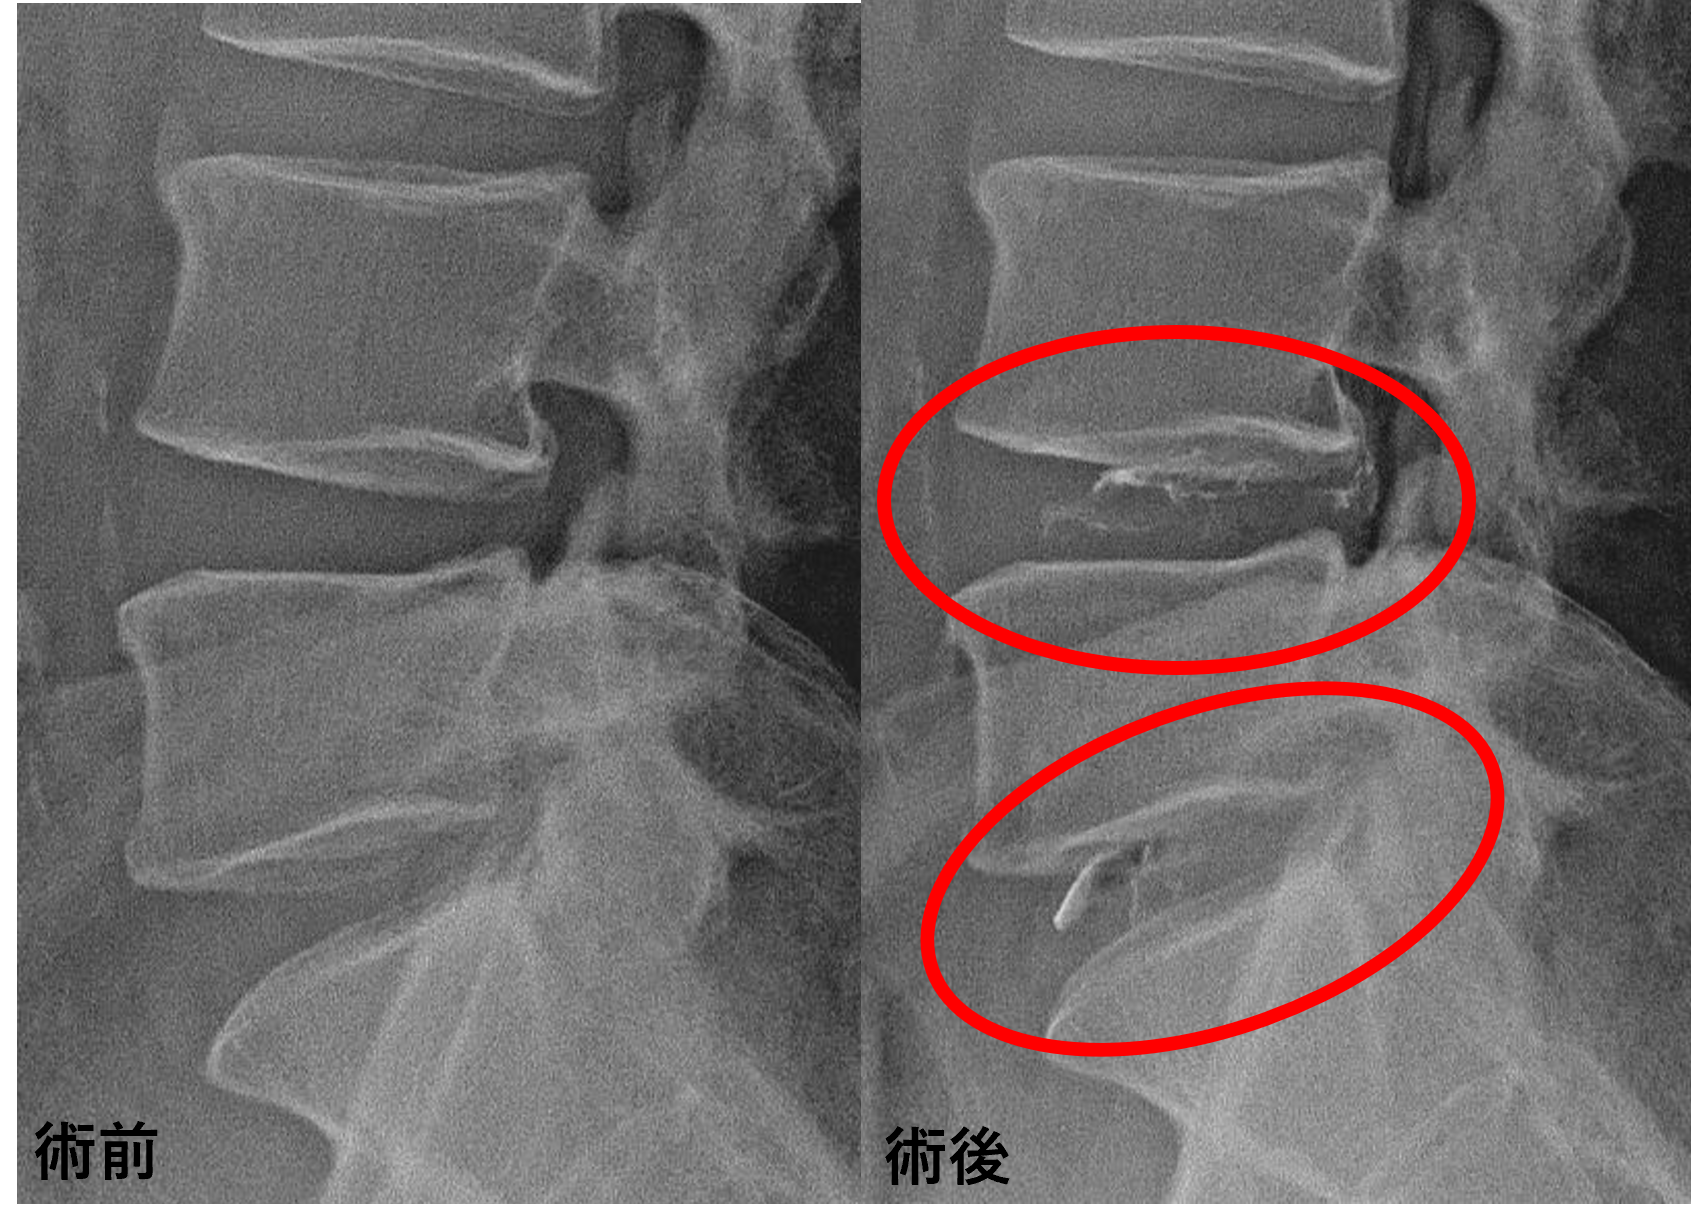

画像及び所見について

- L4/5、5/s – 椎間板変性、膨隆、椎間孔狭窄

以上のことが画像上認められました。

L4/5、5/sの椎間板所見による脊柱管の圧排が、症状の原因の可能性が高い。

患者様と相談の元、L4/5、5/sにセルゲル法を施行